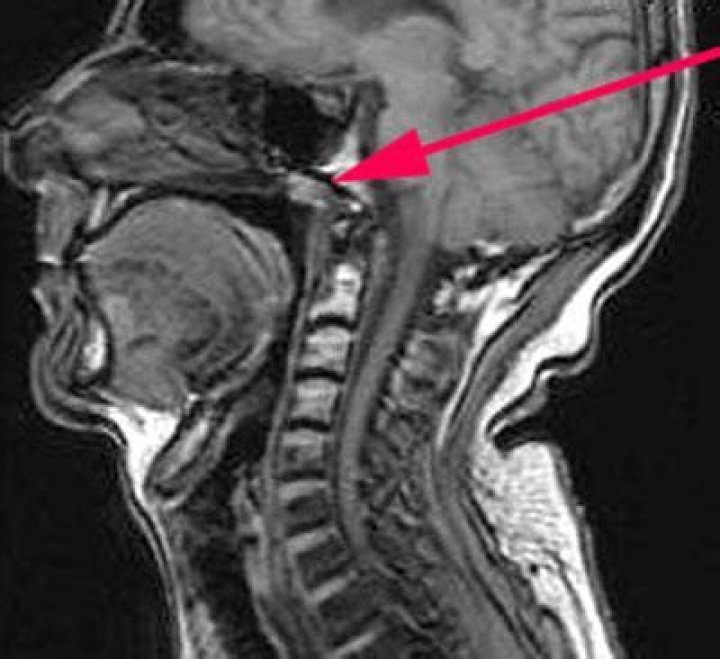

Tornwaldt's cyst is a benign cyst located in the upper posterior nasopharynx. It is a relatively rare lesion and most are small and asymptomatic wher...